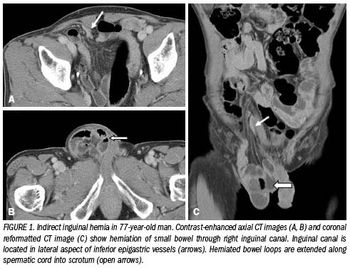

Although most hernias involving the anterior abdominal wall or groin can be diagnosed easily by inspection and palpation, imaging is the principal means of detecting internal, diaphragmatic, and other nonpalpable or unsuspected hernias.1,2